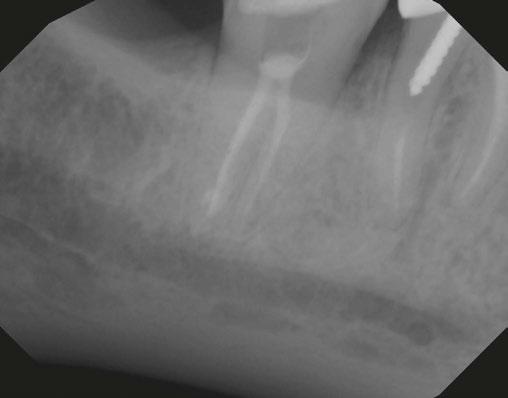

Case 1: Pre-op and diagnosis: A 68-year-old female presented with localized vestibular swelling buccal to tooth No. 30. No. 30 had been symptomatic for a few days, but the swelling started to alarm the patient and caused her to seek treatment. Upon evaluation, No. 30 was diagnosed as necrotic pulp with acute apical abscess. Two treatment options were discussed with the patient: 1) Tooth No. 30 non-surgical root canal therapy or 2) Tooth No. 30 extraction. The patient elected tooth No. 30 non-surgical root canal therapy (NSRCT). A pre-op Small FOV CBCT revealed a heavily calcified pulp chamber and calcified canals and a radix entomolaris. The CBCT revealed PARL’s at the apex of the mesial, distal, and radix entomolaris roots with the lesion extending coronally into the furcation. The patient was advised before treatment that this would be a very challenging case, and No. 30 NSRCT would be given a guarded prognosis, but she chose to proceed with No. 30 NSRCT. Treatment: No. 30 NSRCT, the patient was anesthetized with 68 mg Lidocaine with 0.034 mg EPI via IAN and 68 mg Septocaine with 0.017 mg EPI via buccal infiltration. Rubber dam isolation was utilized, and access was prepared through the PFM crown. 4 canals were located and then immediately after identification of the canal orifices, a platform was created with Soundseal, and the GentleWave Cleanflow handpiece was utilized to help break up the calcified tissue and negotiate each canal, alternating between a pathfile to slowly negotiate the coronal half of the canals and then running the GentleWave CleanFlow Procedure Instrument for 30-40 seconds to remove the accumulated debris. By alternating between files and the CleanFlow with GentleWave, all 4 canals were negotiated to length, and patency was achieved. The final working lengths were between 23 mm-24.5 mm for all 4 canals. All canals were instrumented to a Master Apical File of 20/.04 and obturated with high-flow BC Sealer. By utilizing the GentleWave and High-Flow BC Sealer, the apical delta of the distal root was cleaned, disinfected, and obturated in ways that would not have been possible with traditional endodontic therapy. Post-op: The patient was called 24 hours after treatment and reported she was pain-free, the swelling had reduced, and she was doing well.

9 endopracticeus.com Volume 17 Number 1 COVER STORY